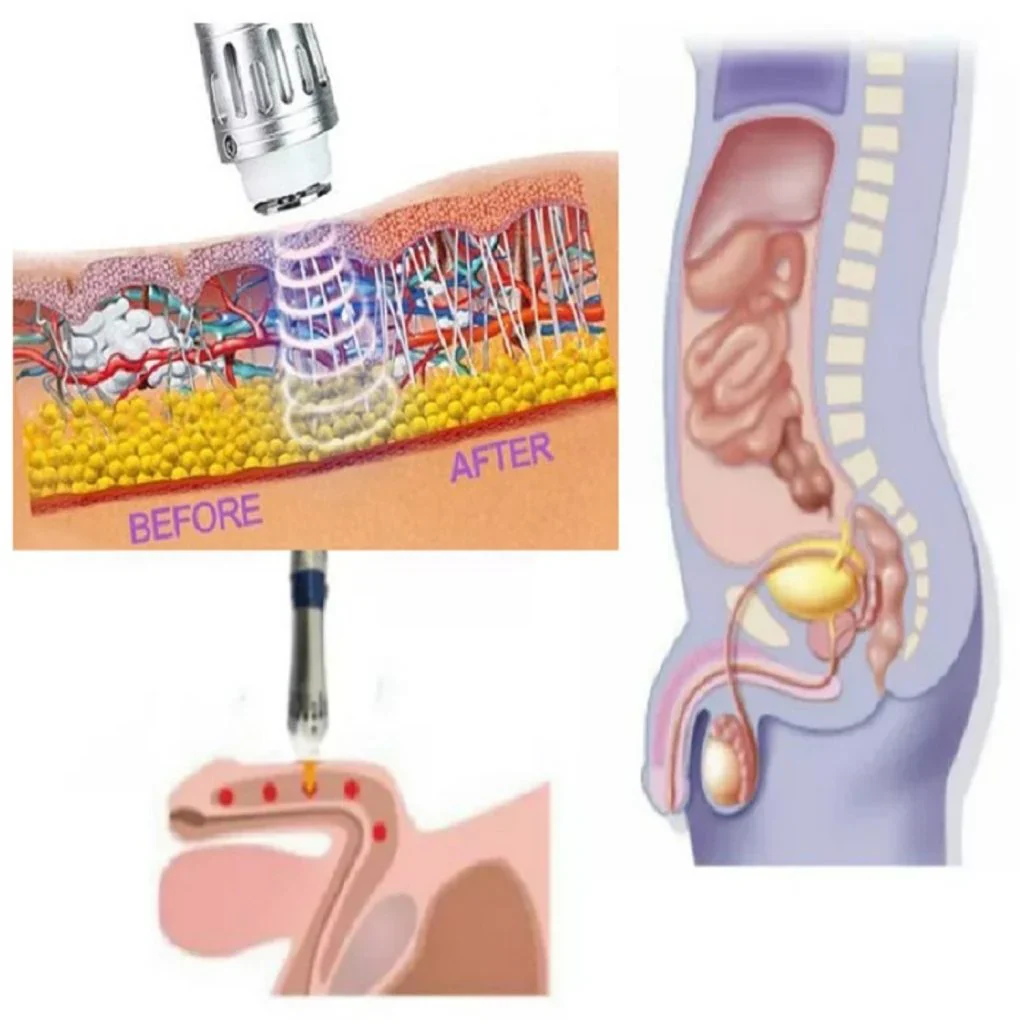

Cómo la terapia ayuda con la disfunción eréctil

La terapia de ondas de choque extracorpóreas es un tratamiento prometedor y no invasivo para la disfunción eréctil, que aborda principalmente la DE causada por problemas vasculares y mala circulación sanguínea. La terapia utiliza ondas de choque que penetran profundamente en los tejidos objetivo, incluida el área del pene, para estimular los mecanismos naturales de reparación. Esto se logra mediante la expansión de los vasos sanguíneos y el aumento del flujo sanguíneo, crucial para lograr y mantener las erecciones.